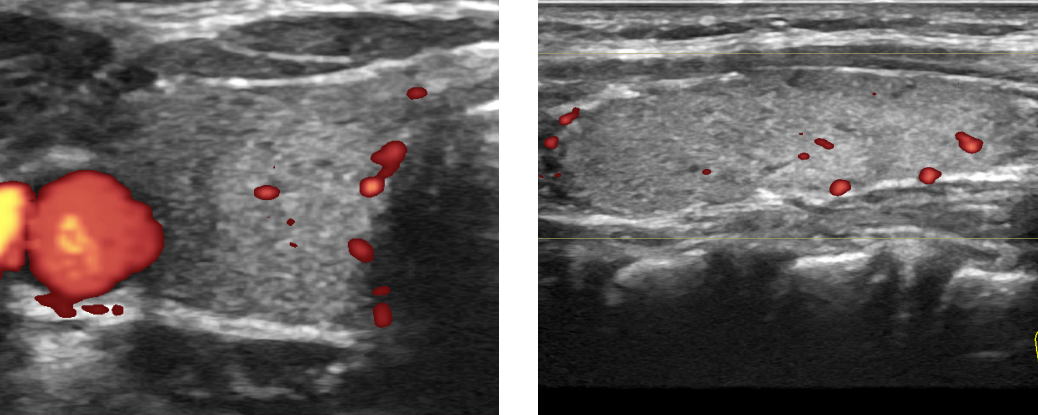

В качестве диагностики мы используем такие методы, как гинекологический осмотр, УЗИ, исследование мазков и бакпосев. В некоторых случаях может потребоваться рентгенологическое исследование.

- УЗИ репродуктивной системы.

Основанием для подозрения о развитии аднексита являются характерные жалобы пациента. Доктор проводит гинекологический осмотр, при котором обнаруживает отечные, увеличенные, болезненные придатки подвижность которых резко ограничена. Гинеколог может назначить клинический анализ крови, мочи, биохимическое исследование. Также проводится ультразвуковая диагностика. При тяжелом течении болезни, может понадобиться, диагностическая лапароскопия.

3. Ультразвуковое исследование внутренних органов в малом тазу, дает информацию о состоянии придатков и помогает выявить беременность.

Пациентке проводится УЗИ половых органов. Возможно назначение гистеросальпингографии – выясняется степень патологического процесса и проходимость маточных труб в период заболевания.